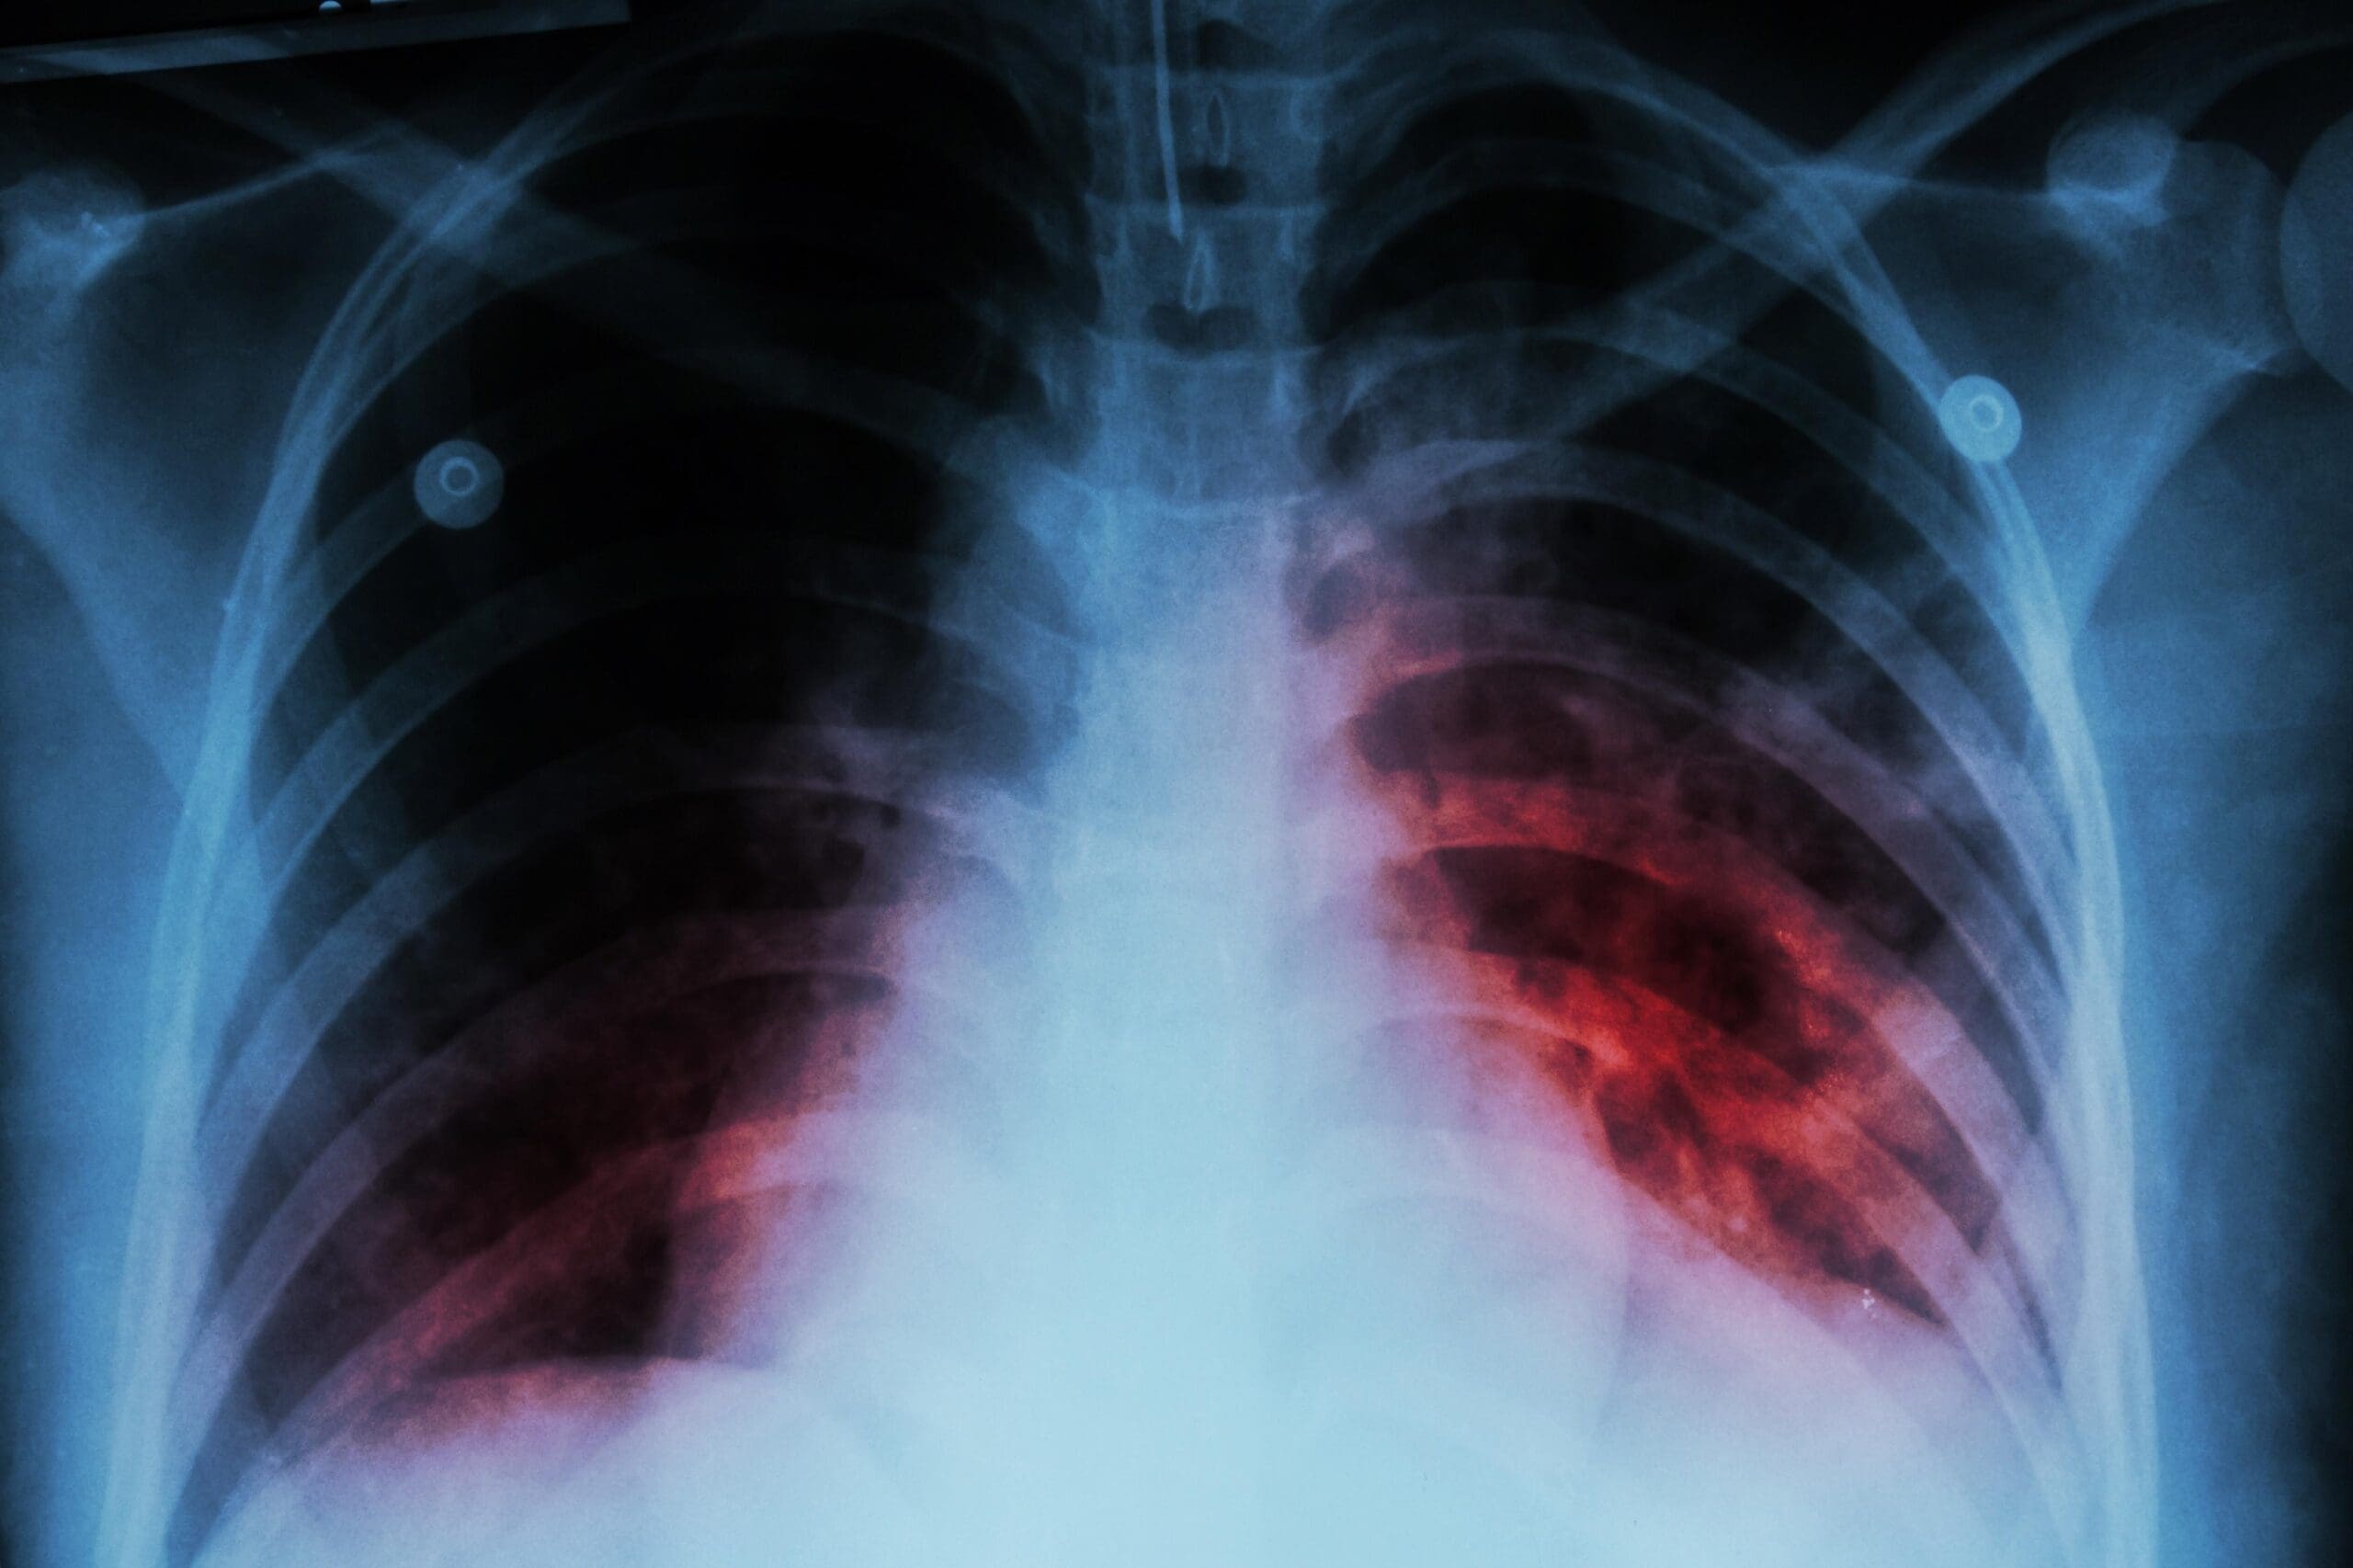

- Rx tórax: masa paravertebral izquierda a nivel de T8-10.

- TAC de tórax: Masa de mediastino posterior al nivel de T9 con invasión de cuerpo vertebral. (Figura No 1)

Figura No. 1 Tac: masa gavabertebral izquierda que aumenta la amplitud del fovamen de conjugación del cuerpo vertebral adyacente ,erosión osea del cuerpo vertebral y del pediculo.feocromocitoma Extr-adrenal.

Durante la hospitalización prequirúrgica presenta una emergencia hipertensiva que se maneja con bloqueadores beta, desarrollando un shock vasoplejico, edema pulmonar y gran labilidad en la tensión arterial; es manejada en UCI con ventilación mecánica, monitoría invasiva (SWAN GANZ) Y con nitroprusiato-nitroglicerina alterados con inotrópicos tipo adrenalina y dopamina, hasta estabilizar la tensión y resolver el edema pulmonar.